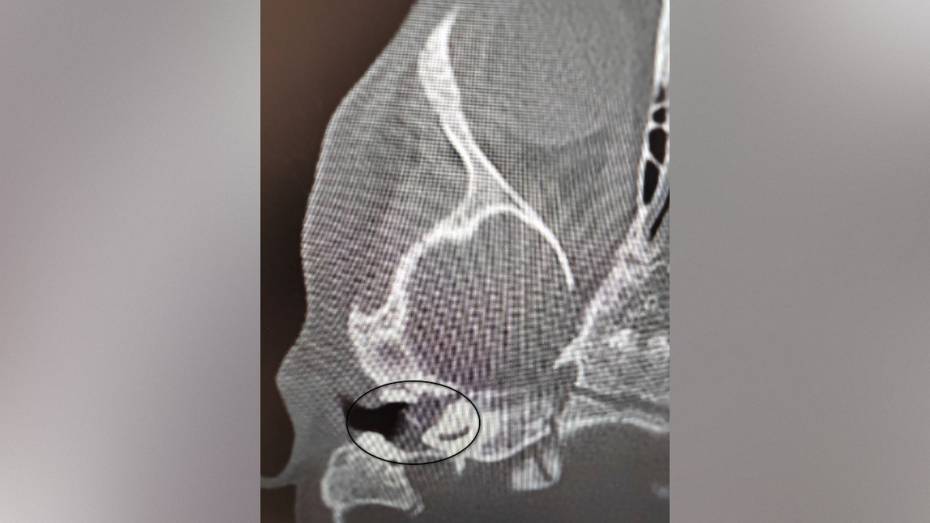

Врачи Воронежской областной детской клинической больницы №1 (ВОДКБ №1) вылечили редкое заболевание у двухлетней пациентки и смогли сохранить ее слух. У ребенка был правосторонний хронический гнойный средний отит и подозрение на врожденную холестеатому барабанной полости (кистозное патологическое образование в среднем ухе. – Прим. ред.). Это заболевание встречается особенно редко в таком раннем возрасте. Из-за холестеатомы девочка могла потерять слух. Об этом сообщили в пресс-службе министерства здравоохранения Воронежской области в среду, 5 ноября.

Как сообщили в министерстве здравоохранения области в группе Вконтакте, после ОРВИ у ребенка появилась боль в ухе. Консервативное лечение не принесло результатов, ситуация осложнилась парезом лицевого нерва – слабостью мимических мышц. Врачи приняли решение о хирургическом лечении. Заведующий оториноларингологическим хирургическим отделением Антон Мащенко провел сложную операцию, под контролем операционного микроскопа он удалил холестеатому, провел декомпрессию лицевого нерва и восстановил механизм звукопроведения.